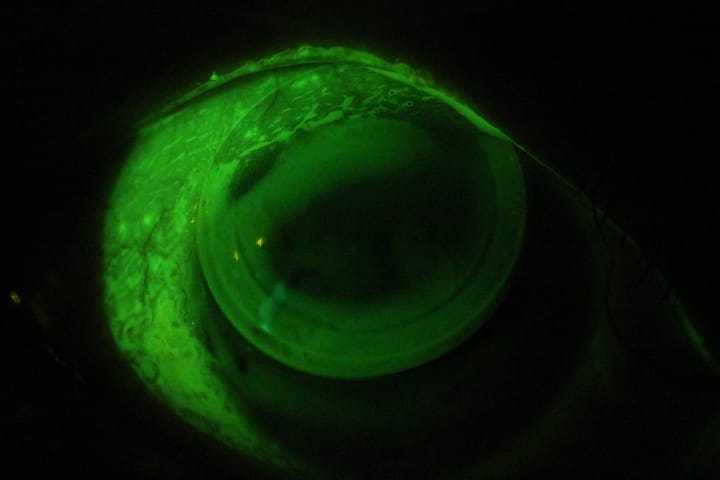

Lente escleral en curva intermedia deficiente.

Zona escleral ajustada

Huellas de lente escleral Ajustado (Neovascularización).